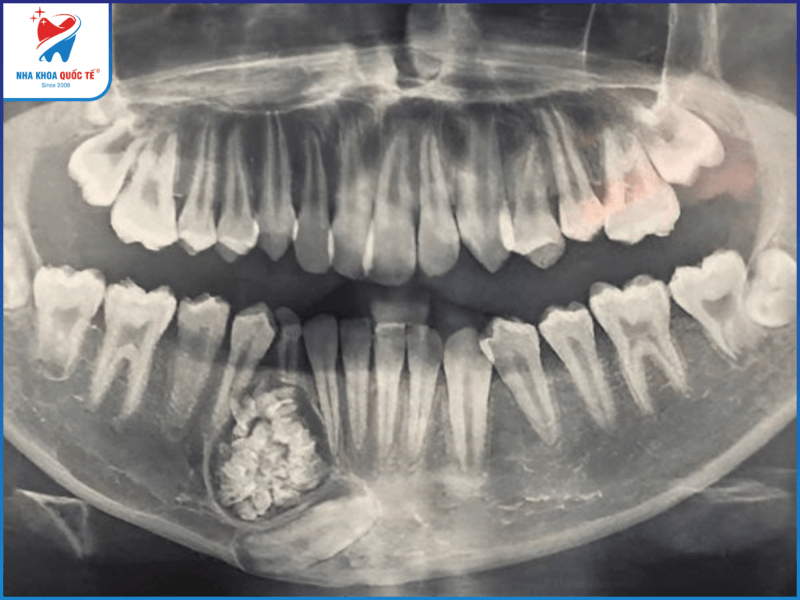

Thông thường u răng là những khối u lành tính, không gây ra triệu chứng và không có những biểu hiện rõ rệt. Hơn một nửa số trường hợp phát hiện ra tình trạng u ở răng khi chụp X quang. Theo nhiều báo cáo khác nhau, tình trạng u ở răng hiếm khi làm gây sưng hàm. Biểu hiện phổ biến nhất của tình trạng u ở răng là sự hiện diện của một chiếc răng vĩnh viễn ngầm hoặc thiếu răng.

U răng thường được phát hiện thông qua chụp X quang

- Chụp X-quang xương hàm